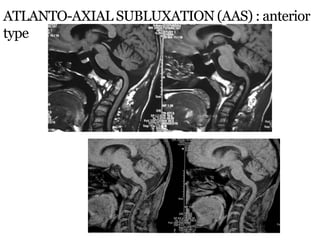

ATLANTO-AXIAL SUBLUXATION (AAS) : anterior

type

 X-rays in neutral position will miss AAS in 48%.

 Controlled flexion views always to be done